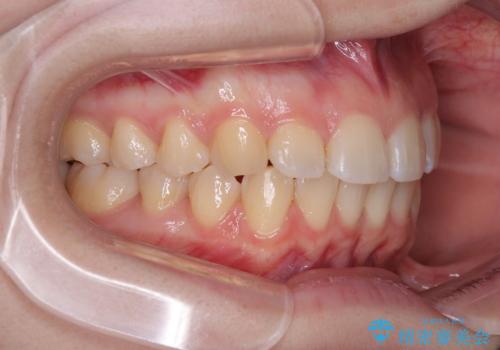

左上の前歯が出ているのが気になる 審美装置による非抜歯ワイヤー矯正

- 左上の前歯が出ていることを主訴として来院された患者様です。

当初はインビザラインを希望されていましたが、職業柄お茶する機会が多く装着時間を確保することが難しいとのことで、相談の上ワイヤー矯正の中では目立ちにくい審美装置で矯正を進めていくこととしました。